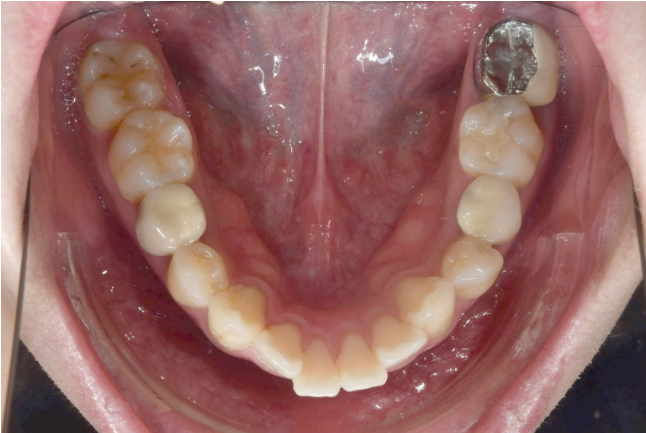

2022.12월 돌출입을 주소로 내원한 환자분 입니다.

앞니 중심선이 어긋나있고 앞니 기울어짐이 보입니다.

2022.12

앞니가 상당히 뻗쳐있는 상태 뻗침과 돌출이 심해서 입이 잘 안다물어지는 상태였고 골격분선상 골격성 2급 부정교합 (무턱)도 있습니다.

앞니가 뻗쳐있는 심한 돌출입은 당연히 발치교정을 해야합니다.